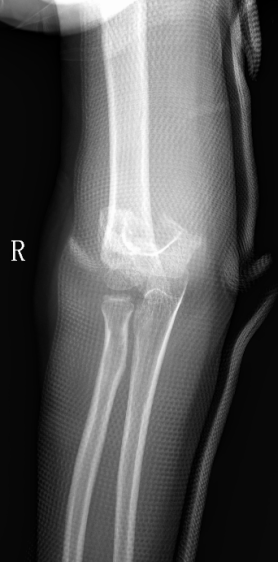

2、小雨(化名):女、8岁、在小区游乐场吊单杠时不慎摔伤致右肘部肿痛、畸形、活动受限1小时就诊我院。(下图为患儿术前X线片)

麻醉下手法整复经皮钢针内固定,术后患儿恢复良好。(下图为患儿术后X线片)